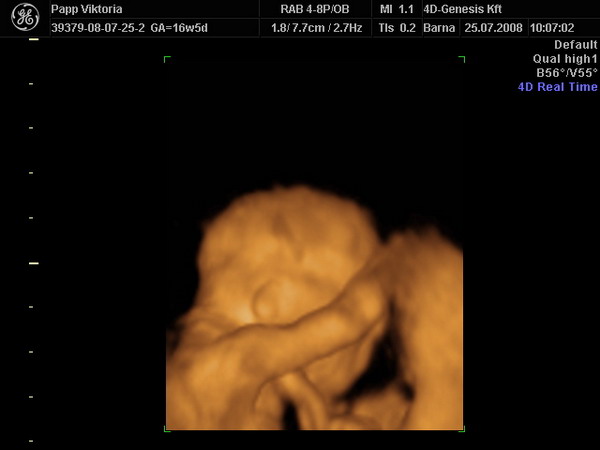

sziasztok! Szuper volt a 4D és KISFIÚ :lol: :lol: :lol: :lol: :lol:

Kép buksi

Kép kis csomag:)

Kép pofi, pocak és kukac:)

Vicky, nagy Gratula a kis Tököhöz! :) Olyan kis édes :) Az enyémet most épp az Apja eteti :), úgyhogy kaptam pár perc "magányt" :) Akartam is kérdezni, hogy hova mentek 4D-re, de látom a Genesisben voltatok :) Jó választás :)